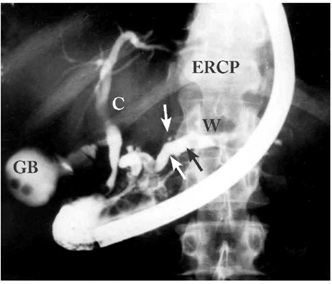

- ב-ERCP (Endoscopic retrograde cholangiopancreatography) אפשר להדגים פתולוגיות אחדות. אפשר להבחין כי צינור הלבלב כולל היצרויות והתרחבויות לסירוגין (תצלום 7.9), ואפשר להדגים אבנים בתוך צינור הלבלב (תצלומים 8.9 ו-9.9).